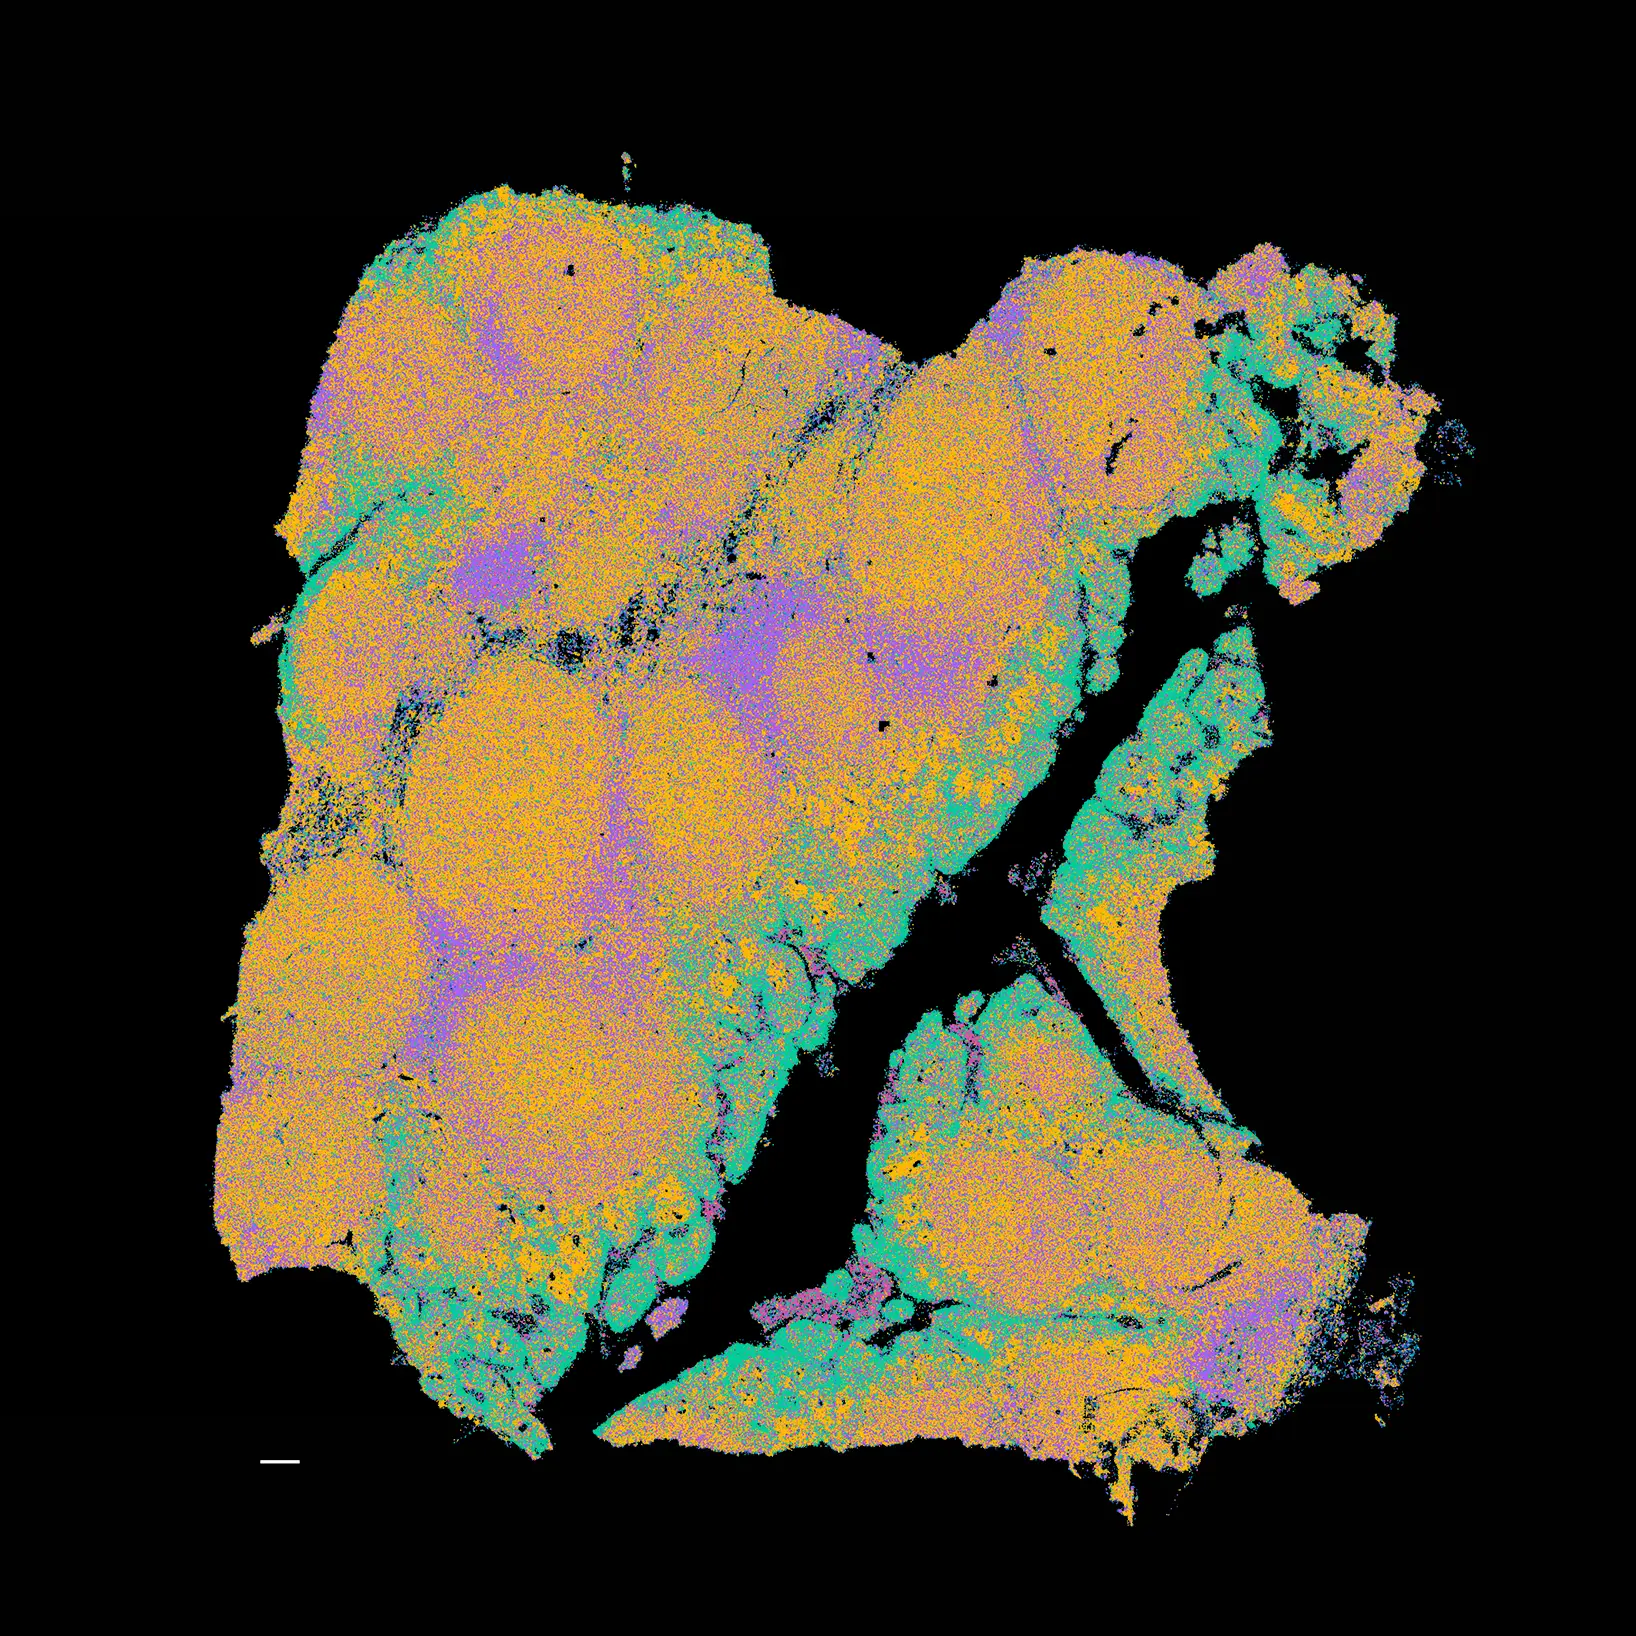

Protein, transcript and fH&E readout of kidney tumor FFPE serial sections (10x10mm). Data generated on a single flow cell.